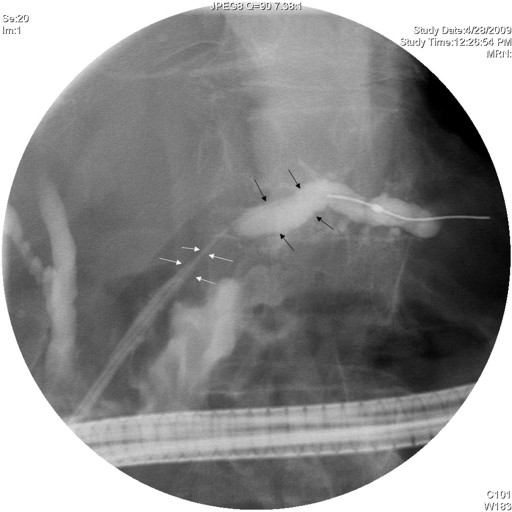

A 57-year-old man with a one year history of alcohol-induced chronic pancreatitis presented with a 1-month history of intermittent epigastric pain. He denied any associated nausea, vomiting, diarrhea, weight loss or other gastrointestinal symptoms. His past medical history was significant for hypertension, type 2 diabetes mellitus, dyslipidemia and chronic obstructive pulmonary disease. The abdomen was soft and non-tender. The liver and spleen were not felt, and no abdominal mass was appreciated. His physical examination was otherwise unremarkable. Laboratory evaluation revealed serum amylase of 356 U/L (reference range: 30-111 U/L) and a lipase of 679 U/L (reference range: 46-218 U/L). Complete blood counts, liver chemistries, carbohydrate antigen 19-9, and alpha-feto protein levels were all normal. Pancreas protocol CT scan of the abdomen revealed a 8x5 cm cystic fluid collection in the left liver lobe, an L-shaped subcapsular fluid collection inferior to right hepatic lobe 10x9 cm in size and a 2.4 cm complex fluid accumulation that involved the head and the superior aspect of the body of pancreas (Figure 1). CT guided diagnostic aspiration of the hepatic cystic lesion drained 100 mL of straw-colored fluid which showed no organisms on gram stain and was sterile on bacterial and fungal cultures. Cytological examination of the fluid did not reveal any malignant cells. The amylase level in this fluid was greater than 51,065 U/L which confirmed the diagnosis of intrahepatic pancreatic pseudocyst extension. At the time of CT guided aspiration, the pseudocyst was treated with percutaneous drainage with the placement of an 8F pig-tail catheter. The intrahepatic pancreatic pseudocyst extension failed to resolve even after 4 weeks of the pig-tail catheter placement (Figure 2). At this point, an ERCP was performed which revealed a normal cholangiogram. Pancreatography revealed a normal-appearing main pancreatic duct to the region of the pancreatic neck, and a ductal stenosis 12 mm in length was identified beginning at the pancreatic body near the neck. The main pancreatic duct and pancreatic duct branches were dilated upstream of the stenosis to about 7 mm (Figure 3). After performing an 8 mm ventral pancreatic sphincterotomy; the stricture was dilated with a 6 mm biliary dilating balloon and a 7F, 10 cm long pancreatic stent was inserted to the tail (Figure 4). Brush cytology and intraductal biopsy specimens were obtained from the stricture and revealed fibrosis and changes of chronic pancreatitis; they were negative for malignancy. EUS examination revealed a pancreatic head cystic lesion extending into the left hepatic lobe (Figure 5ab); fluid examination revealed an amylase of 54,450 U/L and the cytology was negative for malignancy. A follow-up pancreas protocol CT of the abdomen 6 weeks later revealed complete resolution of the pancreatic head fluid accumulation and the intrahepatic pancreatic pseudocyst and decrease in size of the L-shaped subcapsular fluid collection to 2x4 cm (Figure 6). Percutaneous drainage of the remaining L-shaped subcapsular fluid collection was discussed with the patient but he refused any percutaneous or surgical drainage. A follow-up pancreatogram revealed marked improvement in the pancreatic duct stricture. He remains asymptomatic after 9 months of follow-up.

Figure 3. Pancreatography showing main pancreatic duct stricture in the body with dilated branches upstream. |